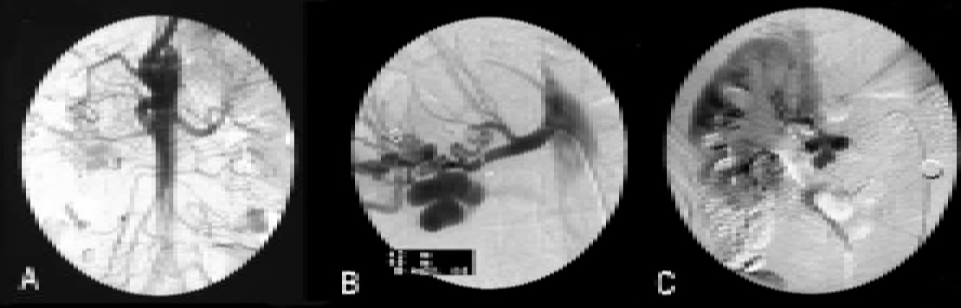

Digital subtraction angiography was performed confirming the 'Bunch of Grapes' appearance of renal artery, which ruled out feasibility of angioplasty due to tight stenoses (figure 3A, B, C).

Figure 3: DSA showing: A) Aortogram with proximal right renal artery, B) Multiple aneurysms arising from mid and distal right renal artery with proximal tight stenosis, C) Delayed nephrogram.